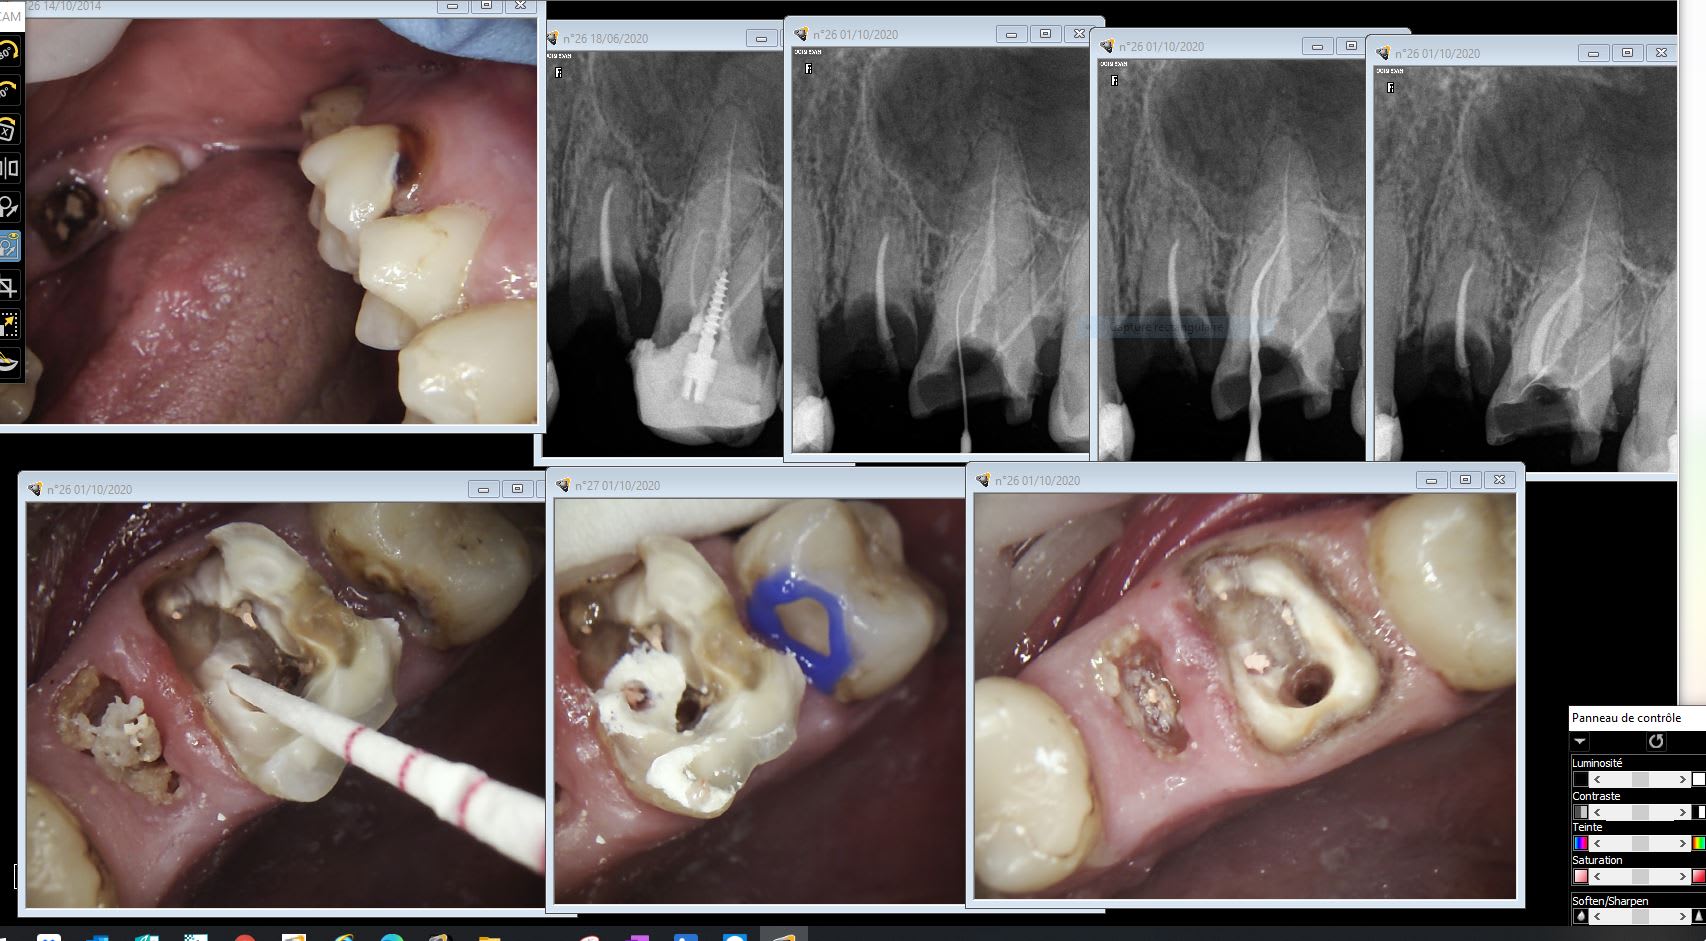

Non j'ai pas fait les endos ( juste une tentative de traitement de MV2) . Je ne refais que la 26 en métal et la 12 qui avait une provisoire + quelques soins extractions et 2 transitoires ( demande du patient esthétique ca r contact avec le public, si si si ). Je vais adresser si il a envie de se faire remettre en place la mandibule, mais c'est pas ça le but de sa visite. Moi je suis pas contrariant surtout avec des patients comme ça.

Bout à bout 4 ourlvo - Eugenol

Hok 1b hgd3rj - Eugenol

Chicot, a quoi sert la résine ultradent block out sur la 7 ??

Chicot , tu nous avez dit que tu ne mettais jamais de clavettes sur tes IC .

sur une molaire comme ça , ça se passe bien ?

Oui mais c’est une couronne métallique , c’est pas fait pour tenir :). J’ai l’impression qu’il y a aussi une petite lésion sur la racine D .

Il a déjà prévu dans sa tête le démontage de la couronne et de l’inlay core. Sans clavette c’est toujours plus sympa à retraiter :)